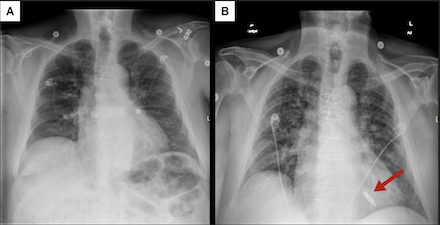

Management: Evaluation included: 1) Chest X-ray which was suggestive of pulmonary edema 2) natriuretic peptide level of 5,500 pg/ml (6-fold increase from 6 months prior) 3) echocardiogram showing EF of 69%, and 4) bilateral lower extremity Doppler ultrasound where he was found to have a large AVF between the right superficial femoral artery and superficial femoral vein. Subsequent right heart catheterization was notable for a PCWP of 18 mmHg and a cardiac output/index of 11 L/min and 5.8 L/min/m2 respectively, hence confirming HOHF. Treatment with intravenous diuretic was initiated and percutaneous stent placement to correct the AVF was performed with symptomatic relief.